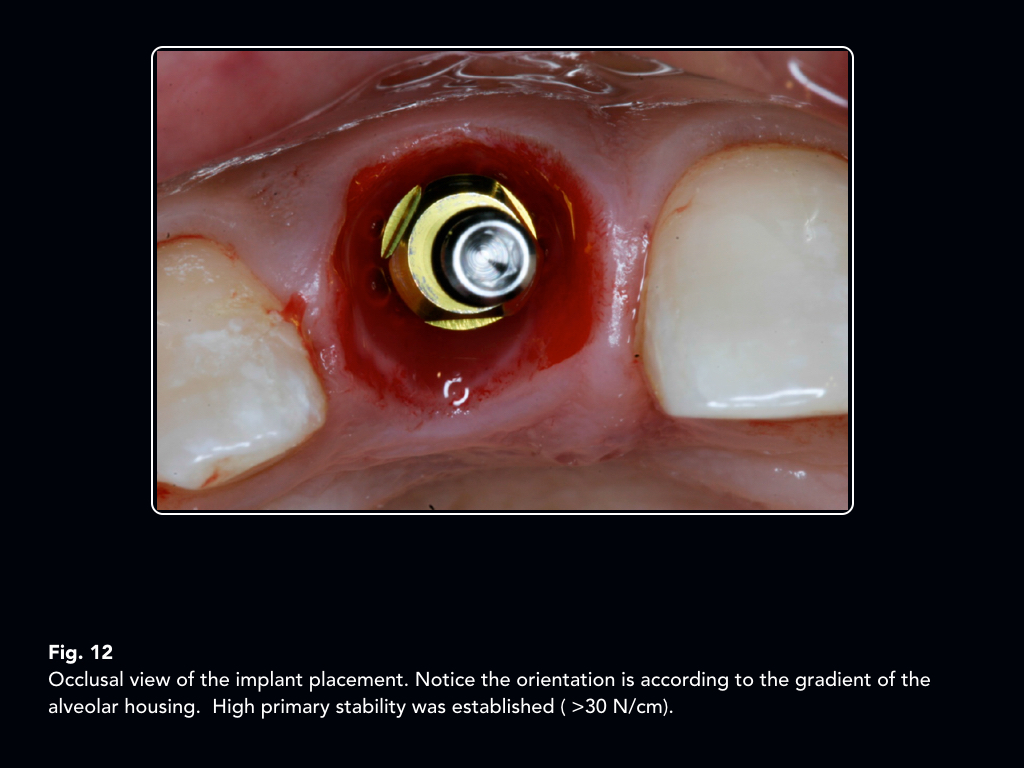

FIG URE 1 4 Preparation steps of the socketshield. Note panel D, the Implant Socket Shield Technique the primary objective of this systematic review was to answer two fundamental questions: the socket shield procedure is a new technique of partial extraction therapy for immediate implant placement. the socket shield technique was developed to preserve bony architecture by leaving a thin shelf of dentin in the. the socket shield technique can be used in. Implant Socket Shield Technique.